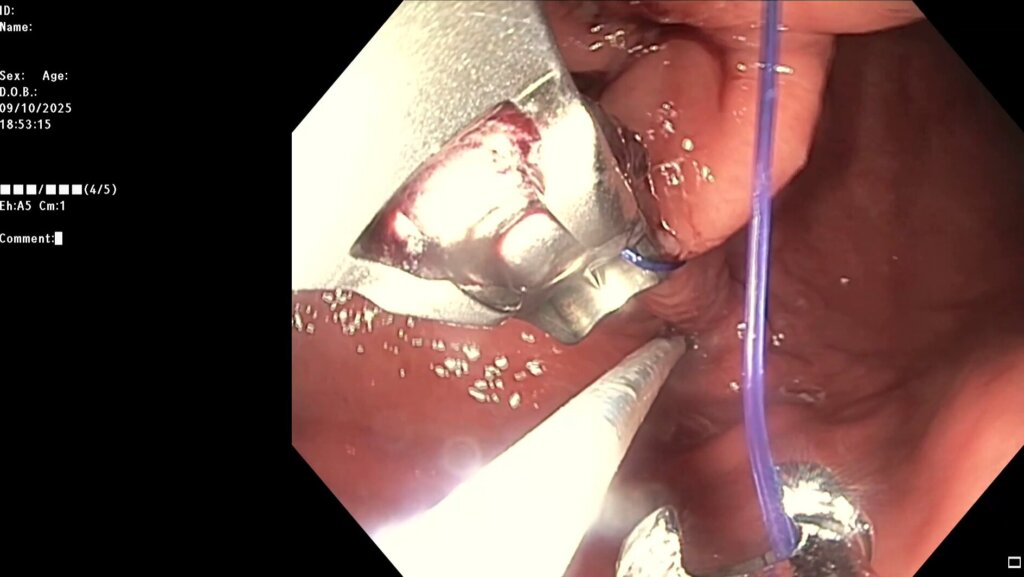

После предварительного обследования произведена операция: ESG + АПК (APC) свода; всего использовано 6 швов, время процедуры ≈ 120 минут.

Под видеоконтролем выполнена эндоскопическая рукавная гастропластика: сшивание стенок желудка при помощи аппарата Overstitch Boston Scientific по длине тела с целью уменьшения объёмов съедаемой пищи.